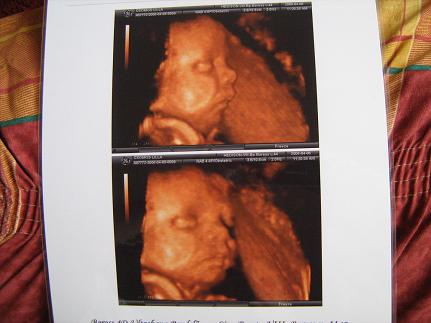

Azért ha tudod, szerintem csináltasd meg, hatalmas élmény. Mi a 31. héten voltunk, amikor már kifejlődött mindene. A Baross utcában csináltattuk (VIII. ker.) és 10.000,- Ft volt. Most is elő szoktam venni a képet és megnézem. Fel is rakok egyet.

Kép 31. héten